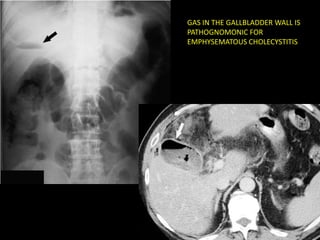

EMPHYSEMATOUS CHOLECYSTITIS

•   Emphysematous cholecystitis < 1%

•   ATC: elderly, male, dbt

•   Mortality rate: 15% (1.4 cholecystitis)

•   TTO: CX because of perforation

•   Test of choice: Abdominal RX

• Air in the biliary system also occurs w/ enteric-

biliary fistula (gallstone ileus or surgical

anastomosis)

– Gallbladder is collpased rather than distended

GAS IN THE GALLBLADDER WALL IS

PATHOGNOMONIC FOR

Emphysematous cholecystitis < 1% • ATC: elderly, male, dbt • Mortality rate: 15% (1.4 cholecystitis) • TTO: CX because of perforation • Test of choice: Abdominal RX

• Air inthe biliary system also occurs w/ enteric- biliary fistula (gallstone ileus or surgical anastomosis) – Gallbladder is collpased rather than distended

GAS IN THEGALLBLADDER WALL IS PATHOGNOMONIC FOR EMPHYSEMATOUS CHOLECYSTITIS